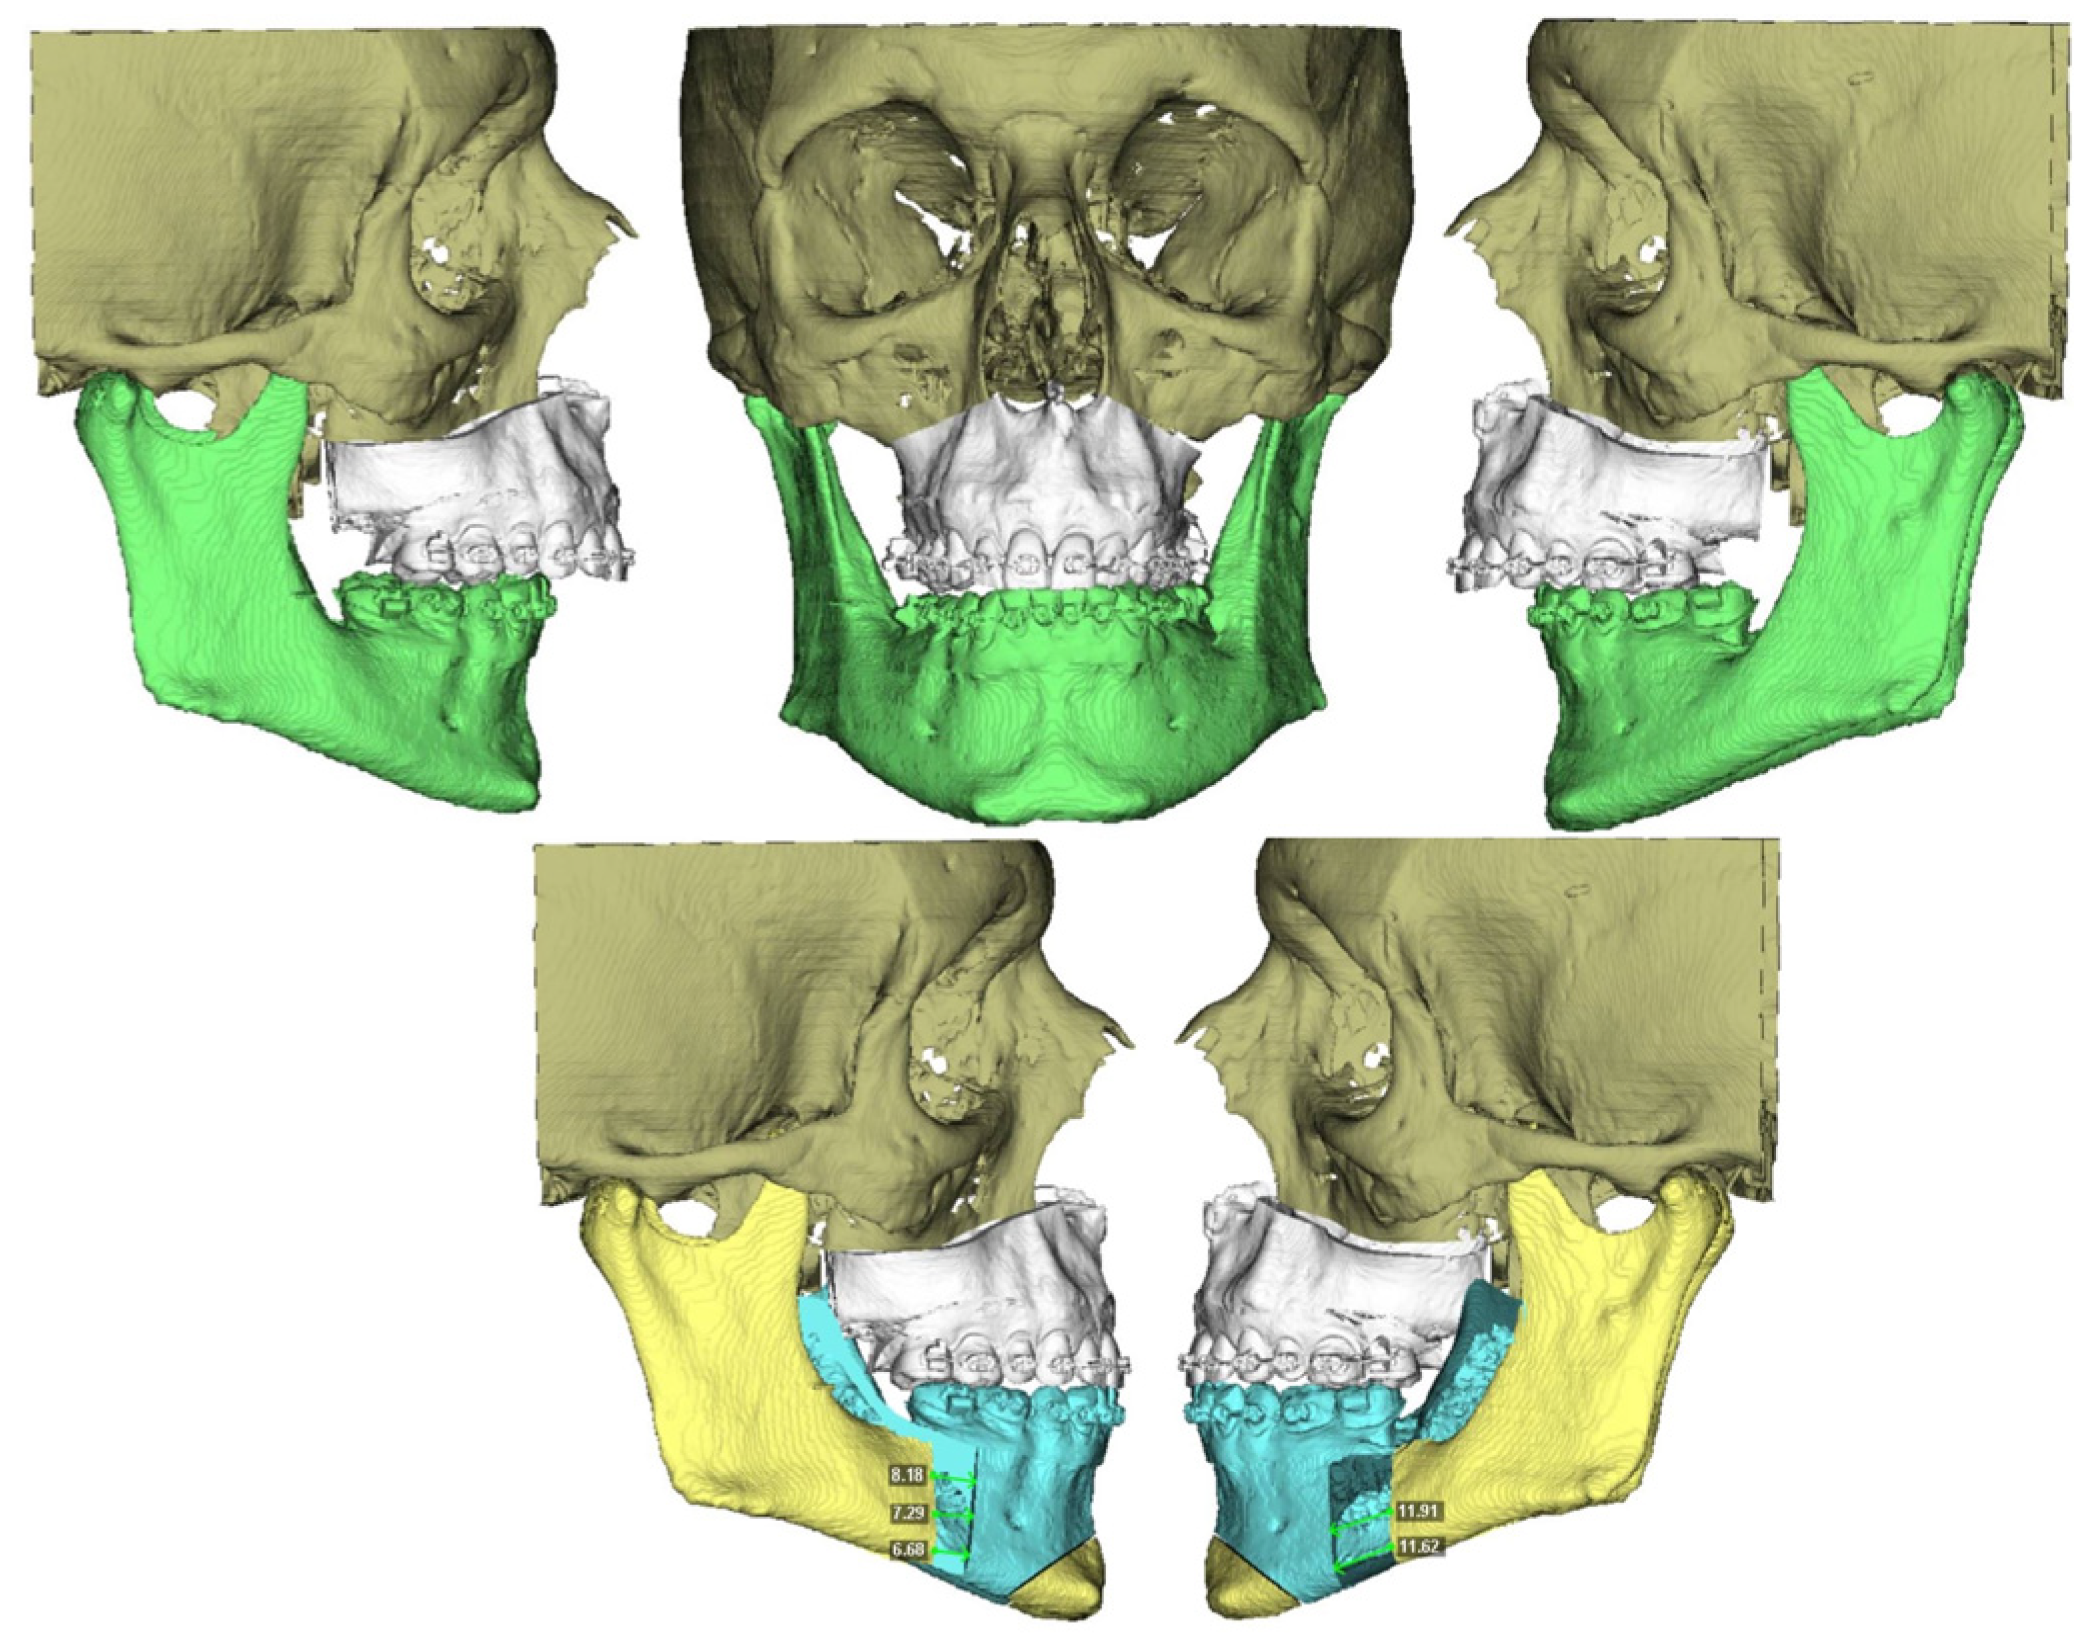

An intraoral incision was designed in the upper vestibule, above the dental apices, extending from the right first molar to the left first molar. The mucoperiosteal flap was elevated to expose the maxilla. The bone-supported cutting guide was then positioned on the maxilla. Two cutting guides were designed, joined at the medial part, each with a tab for positioning on the piriform process. The cutting guide was designed to be fixed with 2.0 mm screws (Figure 3).

A Le Fort-type osteotomy was performed using a reciprocating saw. The maxilla was positioned according to the preoperative planning and fixed with customized titanium plates (Figure 4). The intermediate splint was used to perform a double check of the patient’s correct position of the maxilla and the dental occlusion.

Figure 3. Step 3. Intraoral approach via vestibular sulcus incision and positioning of the maxillary bone-supported cutting guide, corresponding to the first surgical step following VSP.

Figure 4. Le Fort I osteotomy and fixation of the maxilla using customized plates, verifying transfer of the virtual plan to the surgical site.